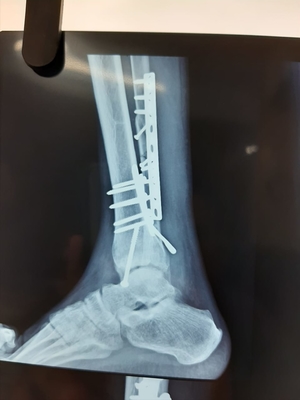

Management of difficult neglected foot and ankle injuries

Presenting an interesting case here:He is 60-year-old active men who met with Road traffic accident 6 months back. He had gross painful swelling in...